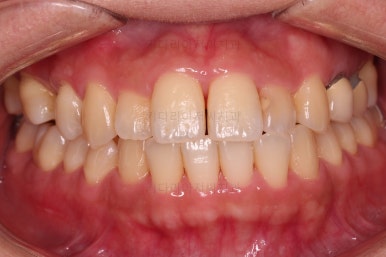

초진 시, 입안의 모습이에요.

결손부위가 눈에 띄고요.

결손부위가 양쪽에 있다보니 윗니 중간에 틈새가 벌어졌네요.

앞니의 약간의 틈새, 약간의 삐뚤어짐, 약간의 중앙선 틀어짐 등 심하진 않으나 약간씩의 문제점들이 있네요.

부산연산동치과 전후 사진을 비교해 보겠습니다.

총 22개월 걸렸고, 임플란트는 1개로 마무리를 했습니다.

처음에 충분히 다양한 치료옵션을 제시해 드렸었고, 입을 넣느냐/마느냐 임플란트를 안하느냐/1개를 하느냐, 기간이 많이 걸리느냐/적게 걸리느냐 등 다양한 관점에서 가장 합리적이다라고 판단되는 옵션을 선택하시어 그에 부합하는 치료로 마무리가 되었습니다.